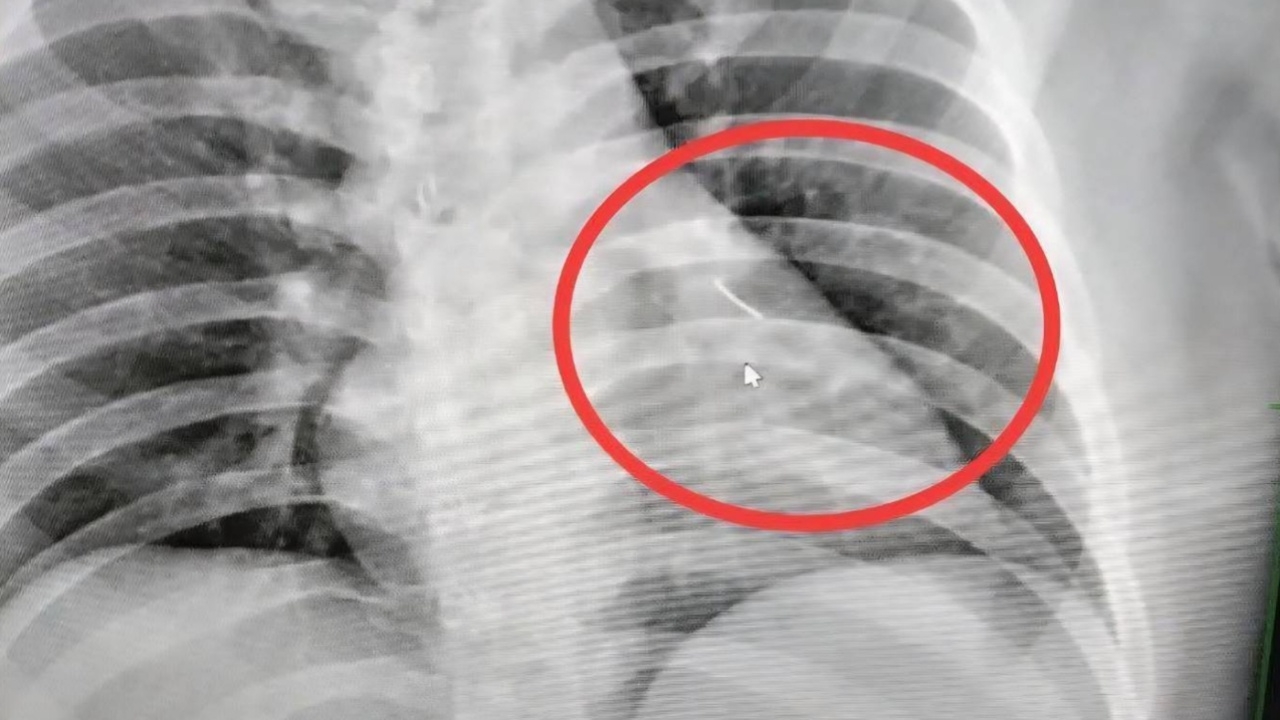

เมื่อไปถึงโรงพยาบาลอาการของนายบุญเลิศ ก็ยังไม่ดีขึ้นหมอจึงนำตัวไปเอ็กซ์เรย์ ปรากฏว่ามีวัตถุคล้ายของมีคมขนาดเล็กความยาวประมาณ 7 ซม.ทราบต่อมาว่าเป็นเข็มเย็บผ้า ฝังอยู่บริเวณหน้าอกซ้ายใกล้กับหัวใจ แพทย์จึงส่งตัวไปผ่าตัดที่โรงพยาบาลศูนย์บุรีรัมย์ เพราะเป็นจุดอันตราย